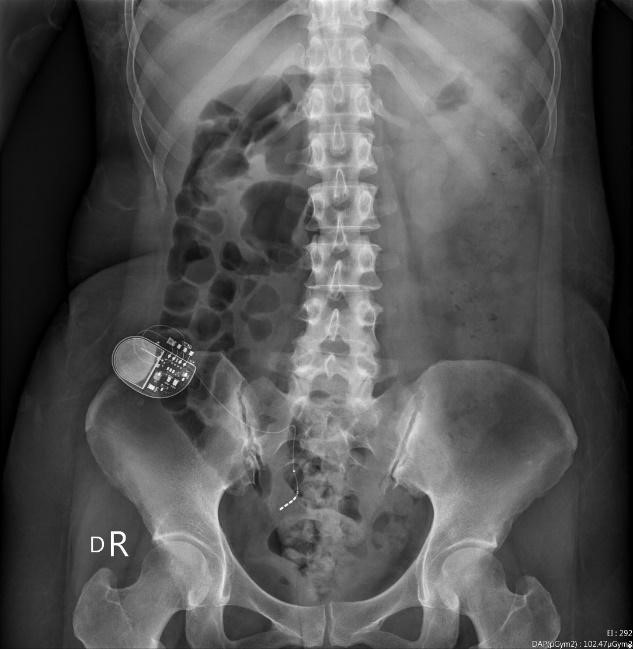

薦神經刺激器植入治療排尿困難、高濃度血小板膀胱注射,研究其是否對於膀胱表皮具有修復作用等。

●薦神經刺激器植入

多項國外轉譯與研究證實透過晶片植入,開啟電刺激的方式,可活化神經增加神經可塑性,以利建立新的神經迴路,改善部份張力,誘發下肢肢體活動,讓復健更為順暢。